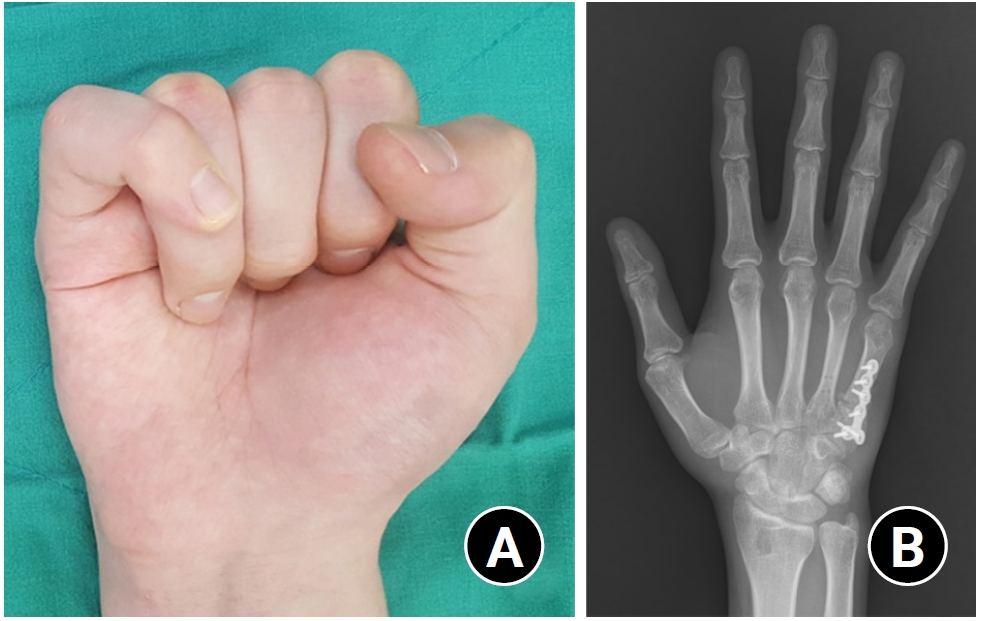

Nonunion is a relatively rare complication in hand fractures due to the rich blood supply, but it can occur commonly in complex injuries such as open fractures with associated nerve, vascular, and tendon injuries, or crush injuries [28]. They are also surgical complications resulting from the disruption of microvascular blood supply around the bone during open reduction or inadequate fracture reduction with a wide fracture gap [23]. Most nonunions in hand fractures are atrophic nonunions, often associated with bone loss or infection [28]. When atrophic nonunion occurs, the nonunited bone should be debrided and treated with rigid internal fixation and autologous bone grafting harvested from sites like the distal radius or olecranon [28]. Hypertrophic nonunion after hand fractures is rare but can be easily treated with more rigid internal fixation alone [28].

In many cases of nonunion, salvage procedures such as arthrodesis or amputation may be necessary to treat associated injuries [23]. Conservative treatments like bone stimulators have not been proven effective to date [23]. Nonunion of the distal phalangeal shaft is relatively common and can be treated with compression screws alone or with bone grafting if the fracture is atrophic [34]. Autologous grafting is the standard technique for nonunion treatment, and cancellous autografts are generally sufficient to stimulate healing [34]. Structural autografts can be used for significant bone defects in the load-sharing portion [34]. Cancellous autograft chips can be compressed in a syringe to create a semistructural bone peg, which may be suitable for most hand fractures [2]. Technically, all atrophic and nonviable bone should be debrided until bone bleeding is visible [23]. Implants used for internal fixation in the nonunion should be slightly larger than those typically used for acute fractures to provide additional mechanical stability [23]. Few studies have reported on outcomes after surgical management of nonunions with internal fixation and bone grafting, and the results are not satisfactory [20,23,27,28,35-37]. Harness et al. [38] reported that, among 25 patients with nonunion (including 15 complex hand injuries), few fingers achieved good function; however, plate-and-screw fixation provided better stability than K-wire fixation. The authors’ experience was similar (Fig. 3).

Fig. 3.

(A) A case with atrophic nonunion and consequent reduction loss. (B) Atrophic nonunion can be treated surgically by stable fixation and autogenous cancellous bone graft.

Fig. 3. (A) A case with atrophic nonunion and consequent reduction loss. (B) Atrophic nonunion can be treated surgically by stable fixation and autogenous cancellous bone graft.